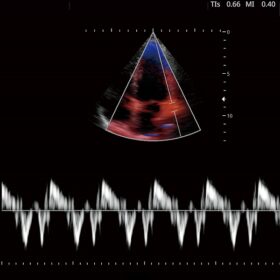

FUTUS features great imaging technologies to support a clear view and confident diagnoses.